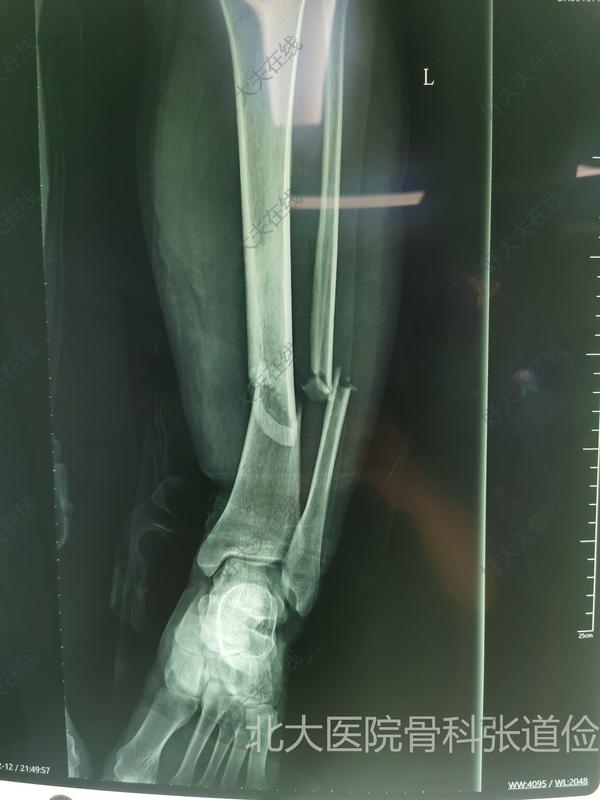

胫骨骨折髓内钉内固定

张道俭医生的科普号

【胫腓骨骨折 】 本病例中国科学院望京医院创伤一科提供(术者:CO接骨专家史医师) 【基本资料】患者:女,36岁 本病例胫骨骨折。 【术前X片】 【术中手术图】【术后X片】